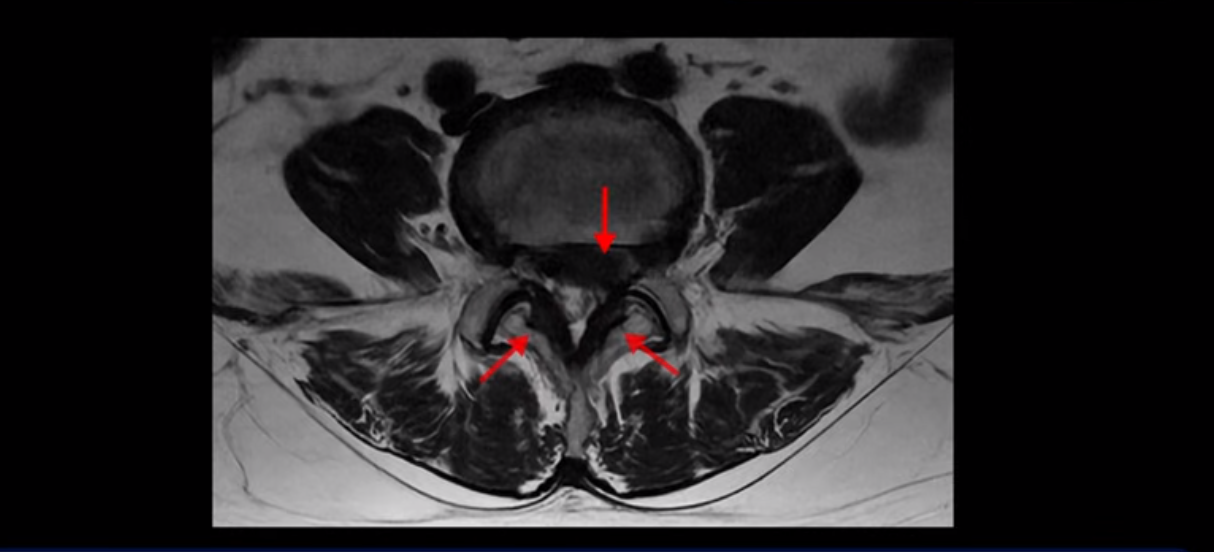

이분 MRI를 먼저 보실까요. 보시다시피 척추 여러 마디가 퇴행되어 있고

4번 5번 마디에는 심한 디스크 파열이 있습니다.

밀려 나온 수핵이 밑으로 흘러내려가 있는데, 이분의 증상은 급성 디스크 증상은 없고 협착증 증상이라서 이 디스크 파열은 오래전에 발생해서 이미 밀려 나온 수핵이 흡수되지 않고 굳어있는 상태로 보입니다.

단면을 보면 디스크 수핵은 왼쪽으로 심하게 밀려 나와 있고

좌우 뒤쪽에는 황색 인대가 두꺼워져 있습니다.

앞에서는 디스크 수핵이 신경 공간으로 침범하고 뒤에서는 두꺼워진 인대가 신경 공간을 좁히고 있습니다.

이렇게 신경 공간이 좁아진 것을 협착이라고 합니다. 왼쪽으로 신경 구멍이 더 좁아져 있으니까 처음에는 왼쪽 엉덩이와 다리가 아팠는데 몇 년 동안 주사 맞으면서 버티다 보니까 오른쪽 다리까지 아프게 됩니다. 결국 양쪽 다리가 너무 아파서 5분 걷기도 힘들어지게 됩니다.